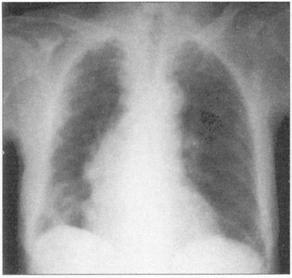

①周围性发绀及周围静脉扩张是由COPD引起的CO2潴留的主要特征(图76)。②脊柱侧后凸常预示患者有某种呼吸系统疾病的倾向(图77)。③结核的X线表现(图78)。④肺尖部结核所致的纤维化多引起上胸部变平(图79),由于脊柱常受累,故多有成角。⑤支气管肺癌(图80)。⑥大叶肺炎患者常伴发单纯疱疹病毒感染(图81、图82)。⑦如肺组织萎陷(如气胸),则胸片上无法看到肺纹理(图83)。

图80 支气管肺癌左肺有一阴影

图81 大叶性肺炎,这个患者有右肺实变